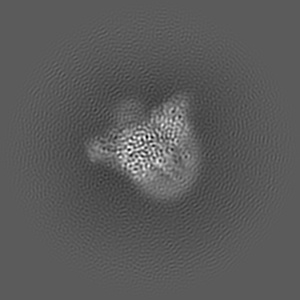

CryoEM structure of mu-opioid receptor - Gi protein complex bound to lofentanil (LFT)

Single-particle3.2 Å

Sample: mu-opioid receptor - Gi protein complex bound to lofentanil (LFT)